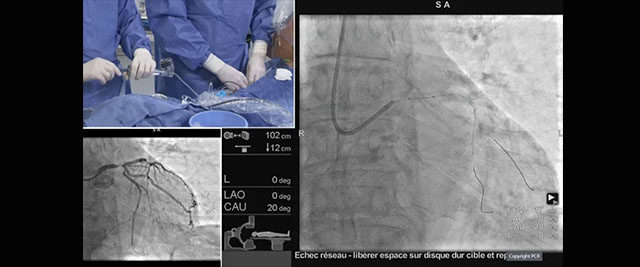

live case a calcified distal lm bifurcation lesion treated by shockwave